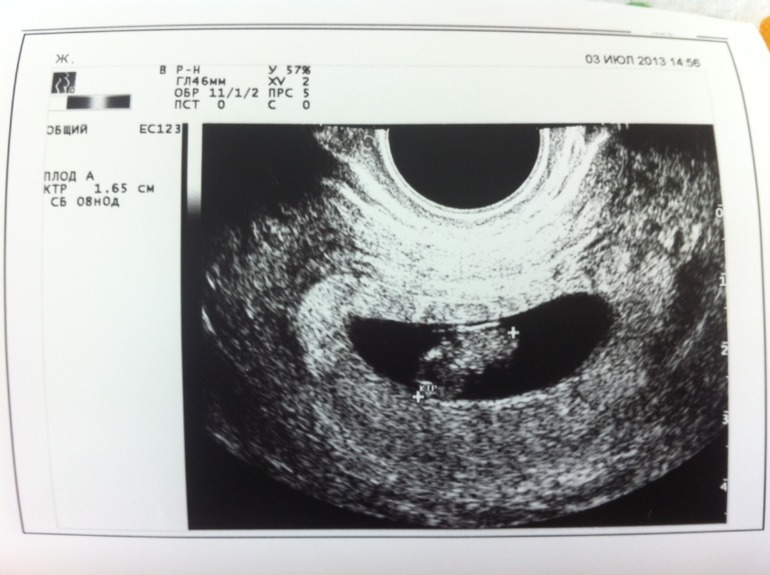

на узи мне дали послушать сердечко !!! Как это клево !!! Я не могу описать словами!!! 16 мм, чсс 168 ударов в минуту, 8 акушерских неделек

Дали снимок моей мааасенькой любви !!!

Я втжу головку и ручку